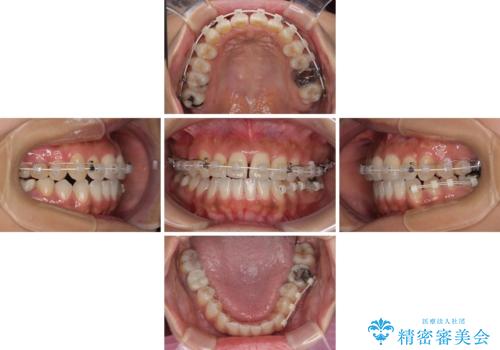

上顎骨の横幅が狭く、歯列が混み合っていたため、急速拡大装置により側方拡大し、咬み合わせと歯列を改善することとしました。

下顎は部分的に咬み合わせに問題があったため、部分的な装置を付けることとしました。

骨格的な問題を解決したことで、下顎は部分矯正で対応することができました。